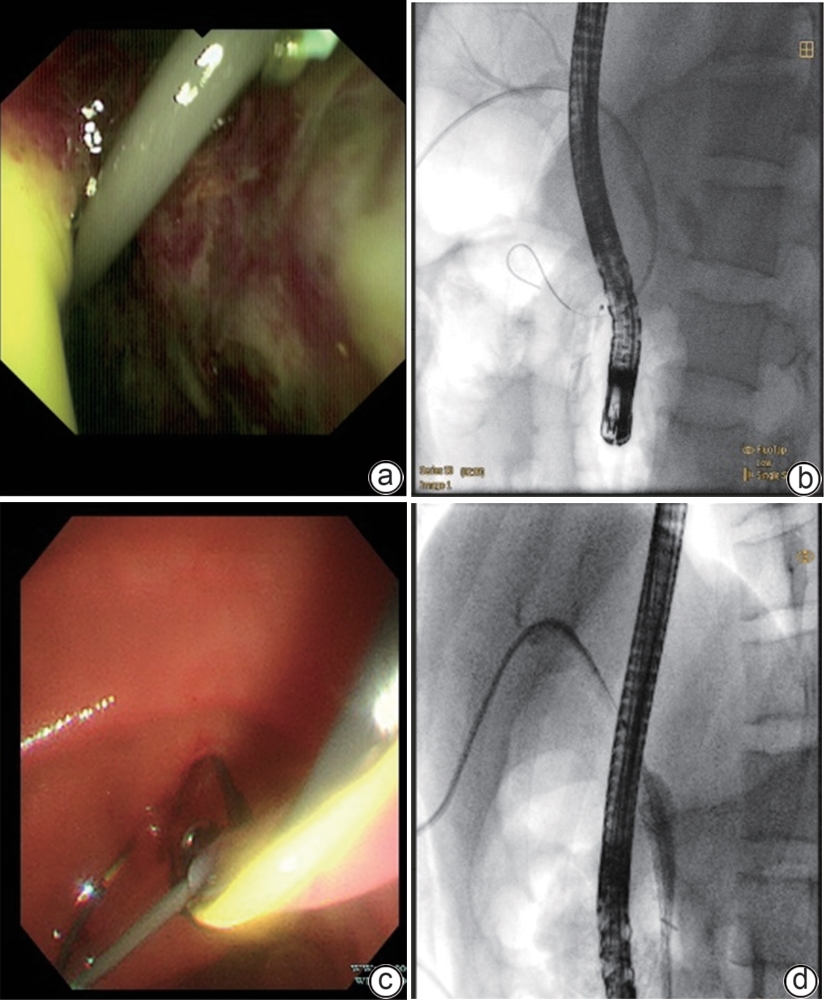

Successful treatment of biliary fistula after Beger surgery by oral choledochoscopy-assisted percutaneous-endoscopic rendezvous technique: A case report

Yuxin WANG, Weigang GU, Zheng JIN, Xiaofeng ZHANG

2025, 41(2): 333-336. DOI: 10.12449/JCH250220

Abstract(861) HTML (246) PDF (4794KB)(49)

Abstract:

Duodenum-preserving pancreatic head resection, also known as Beger surgery, has a high incidence rate of bile duct injury after surgery, while the treatment modality for bile duct injury depends on the severity of the injury, and endoscopic therapy is often challenging in case of severe bile duct injury. Recently a patient with biliary fistula after Beger surgery was admitted to Affiliated Hangzhou First People’s Hospital, Westlake University, and successful diagnosis and treatment were achieved through oral choledochoscopy-assisted percutaneous-endoscopic rendezvous technique.